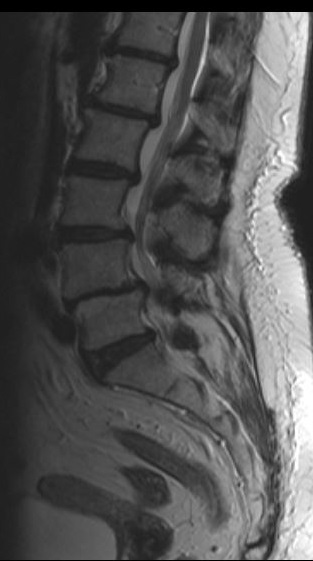

На начальных стадиях стеноз позвоночного канала поясничного отдела ничем себя не проявляет. Но по мере развития болезни обнаруживаются боли в пояснице, понижается чувствительность ног, нарушается походка. Больной не может долго ходить, ему требуется отдых каждые 100-200 метров.

На начальных и промежуточных стадиях заболевания возможно консервативное лечение стеноза позвоночного канала. В таких случаях врач, чтобы снять неприятную симптоматику, назначает лекарственные препараты (обезболивающие, противовоспалительные, стероидные, активирующие кровообращение и обмен веществ), физиотерапевтические процедуры, массаж, лечебную гимнастику, корсетотерапию. Благодаря медленному прогрессированию болезни в большинстве случаев удается затормозить ее развитие.

Если же консервативные методы не дают желаемого результата, прибегают к хирургическому вмешательству.